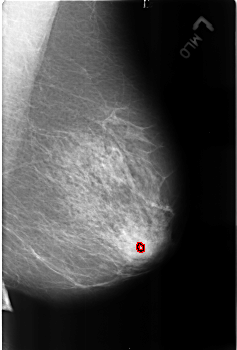

B_3173_1.RIGHT_MLO

FILE: B_3173_1.LEFT_MLO.OVERLAY

TOTAL_ABNORMALITIES 1

ABNORMALITY 1

LESION_TYPE CALCIFICATION TYPE ROUND_AND_REGULAR DISTRIBUTION N/A

ASSESSMENT 2

SUBTLETY 3

PATHOLOGY BENIGN_WITHOUT_CALLBACK